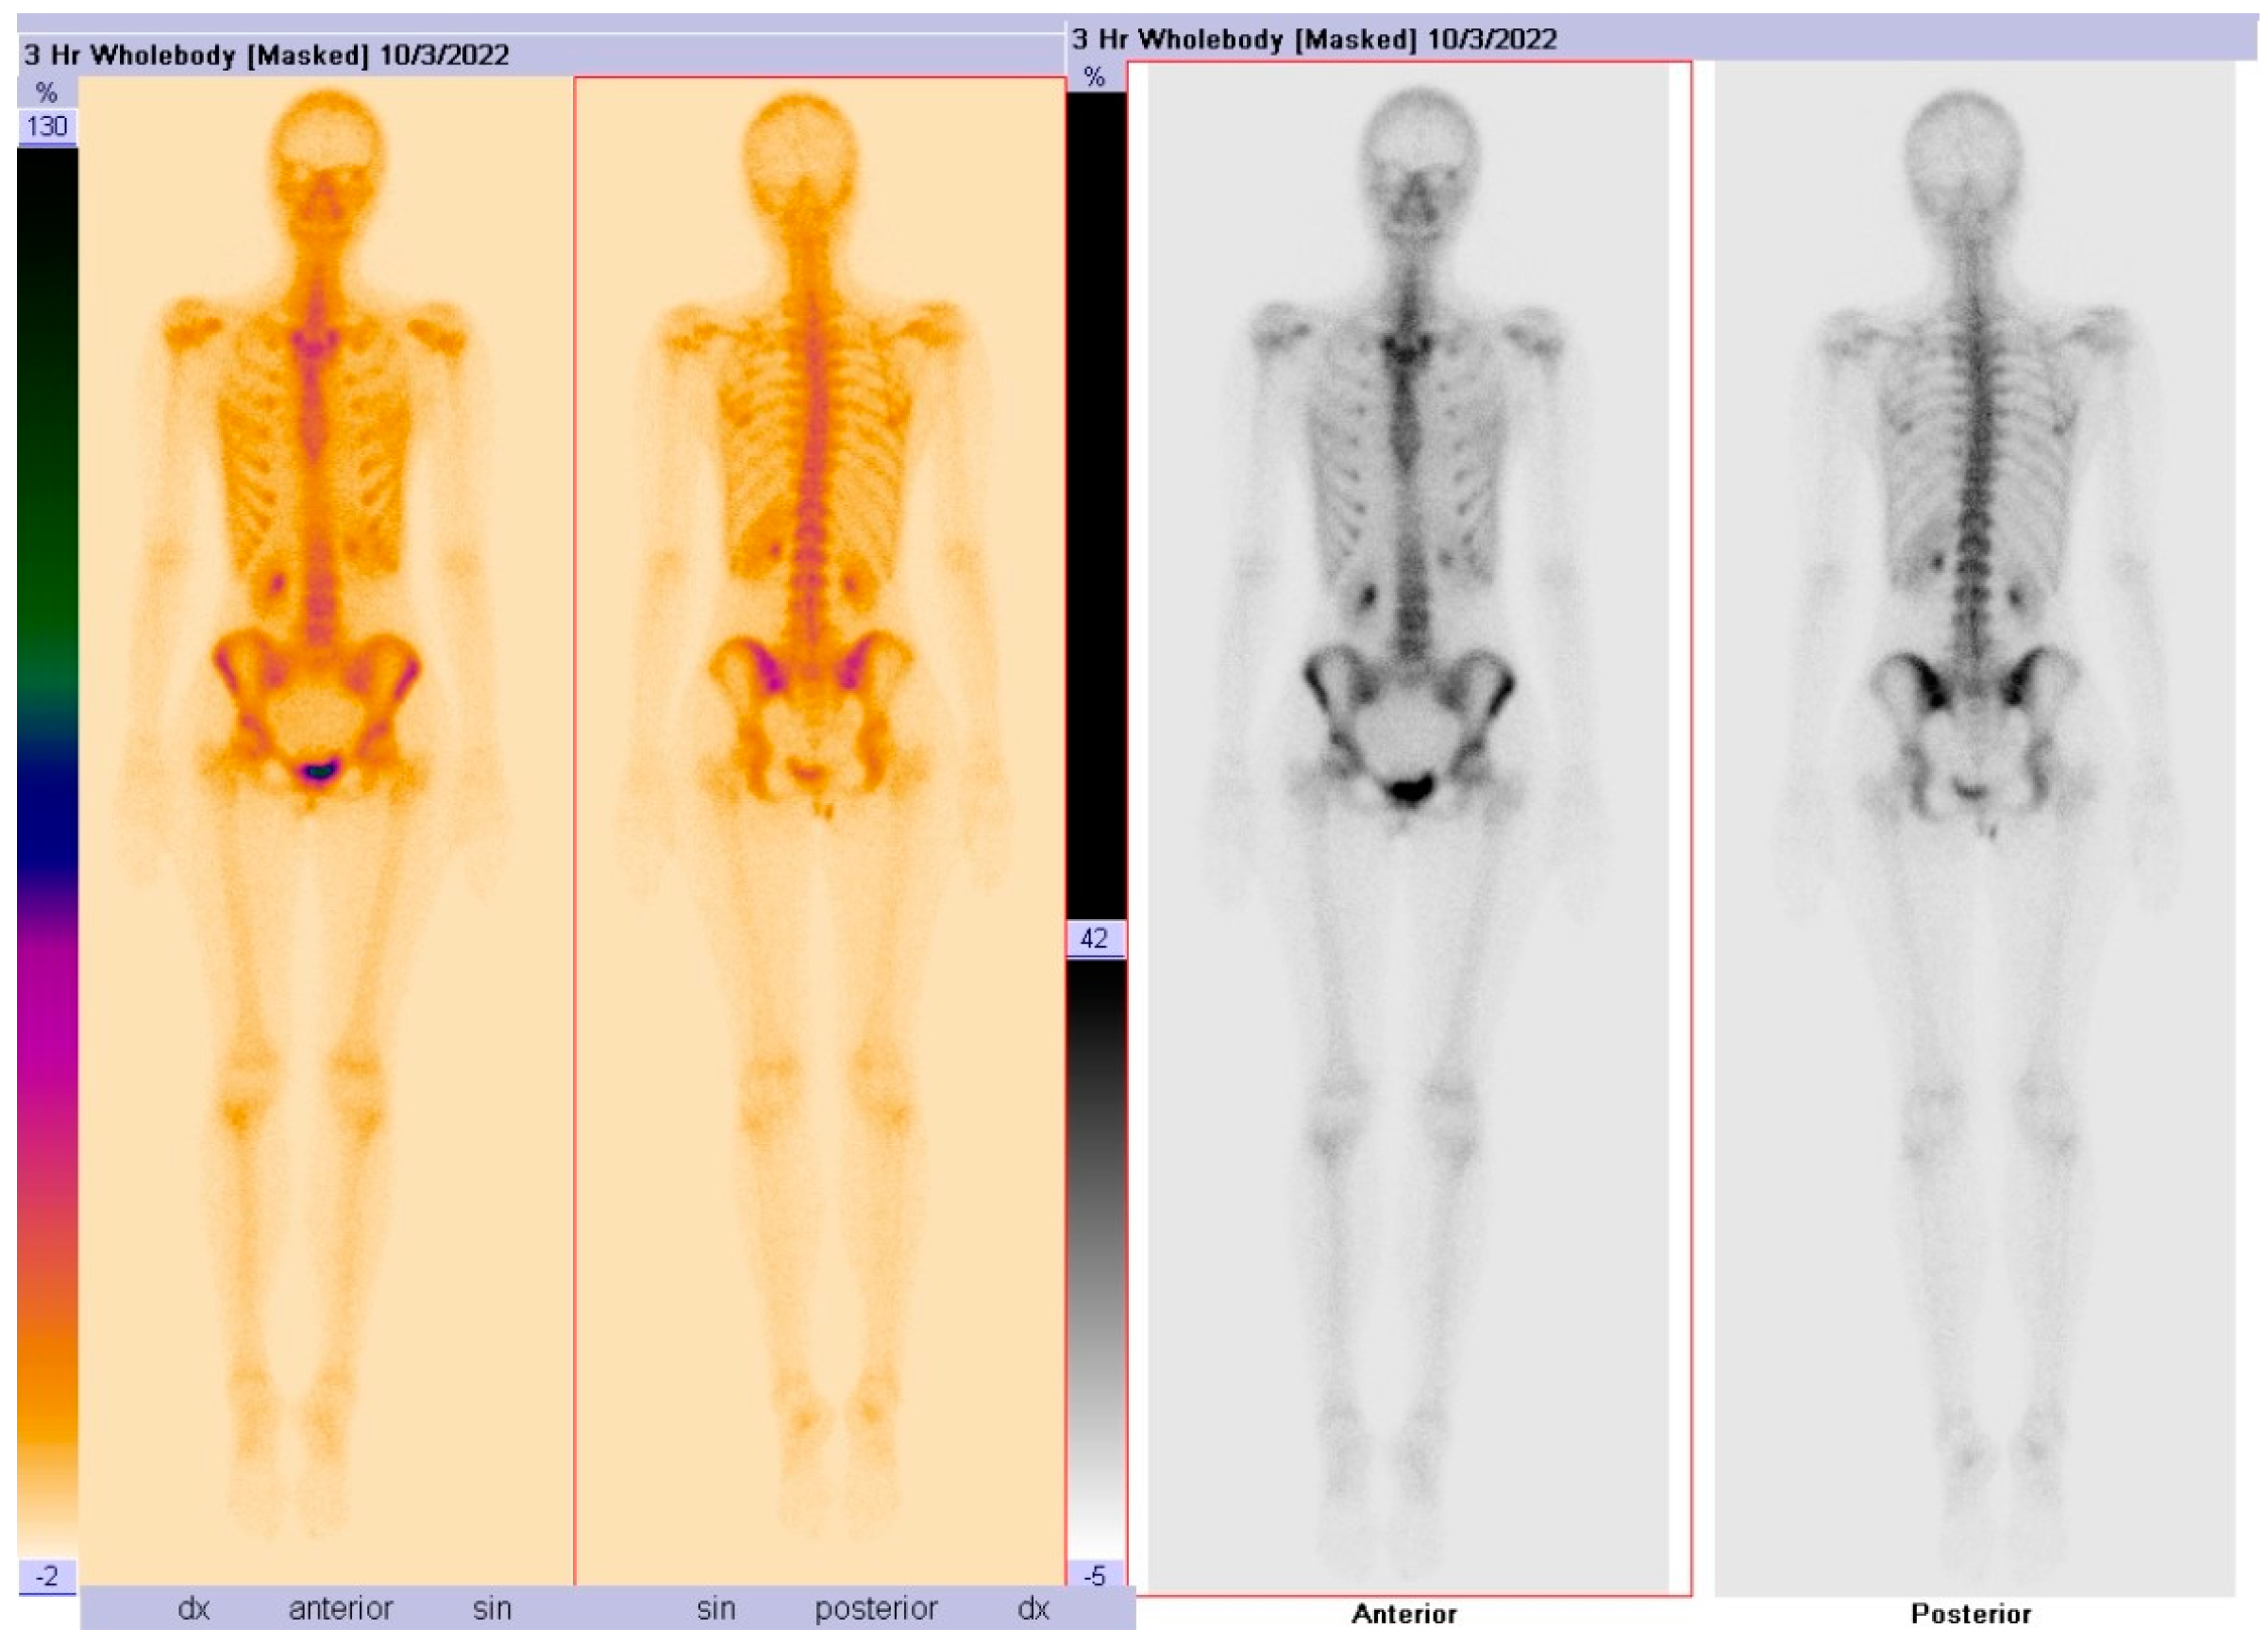

A static skeletal scintigraphy of the pelvic bones was performed, which did not show conclusive evidence of pathological or osteoblastic changes in the bones (Figure 3).

Figure 3.

A static skeletal scintigraphy of the pelvic bones, which did not show conclusive evidence of pathological changes in the bones. No signs of osteoblastic lesions.